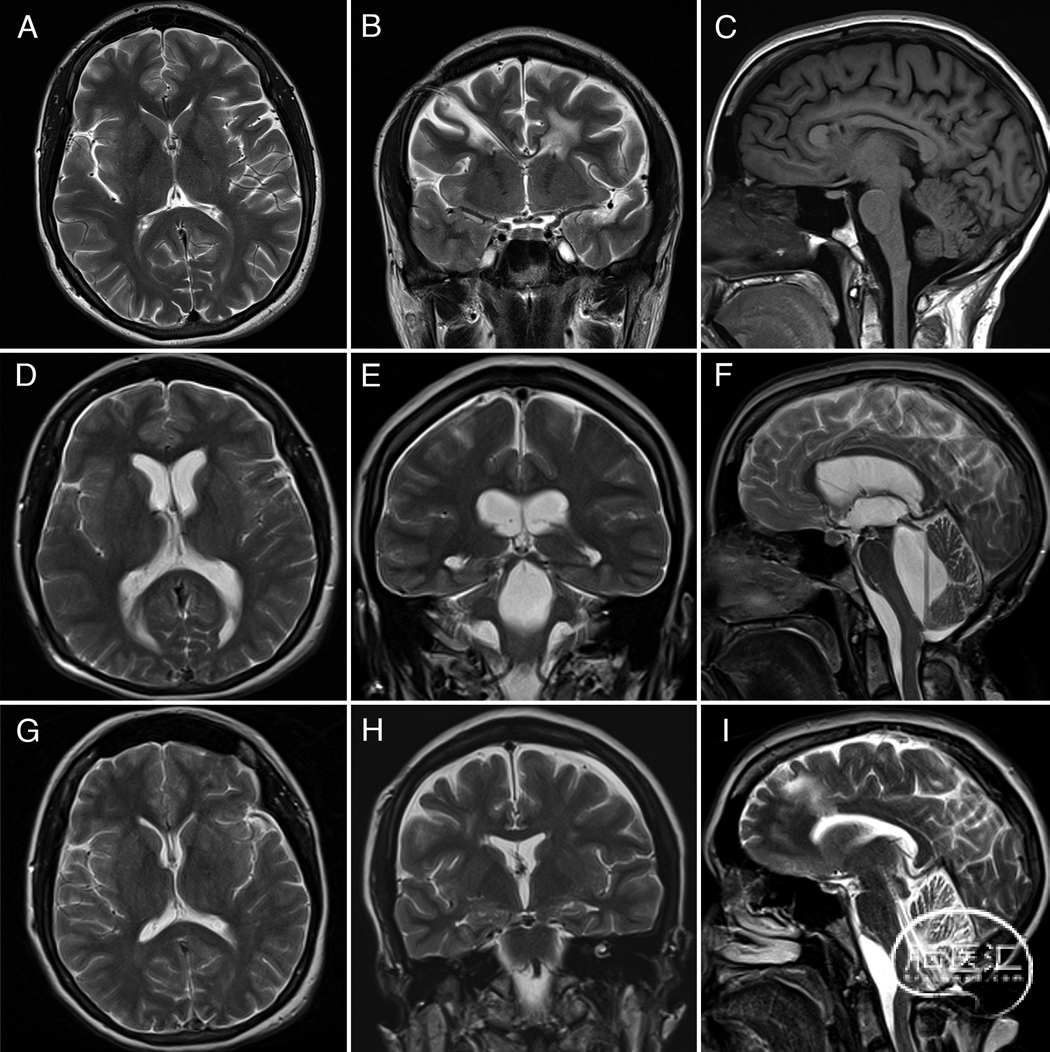

图1展示了病例1的脑室大小变化过程,包括置管后12个月随访影像学表现稳定。图2为分流系列检查中的胸片图像,示意图显示分流阀置于锁骨尾侧的解剖位置。

图1. 病例1。T2加权(A、B及D–I)与T1加权(C)磁共振图像显示脑室扩大进展。A–C:分别为轴位、冠状位及矢状位图像,呈现神经功能正常状态下的基线脑室系统形态。D–F:分别为轴位、冠状位及矢状位图像,显示治疗前脑室系统显著进行性扩大,以第四脑室扩大最为明显。G–I:分别为轴位、冠状位及矢状位图像,展示治疗后1年脑室扩大程度改善,神经系统症状完全缓解: